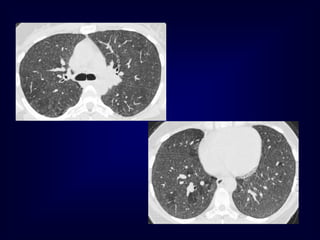

Airway Disease

what you see……

In inspiration

sharply demarcated areas of seemingly increased

density (normal) and decreased density

demarcation by interlobular septa

In expiration

‘black’ areas remain in volume and density

‘white’ areas decrease in volume and increase in

density

INCREASE IN CONTRAST

DIFFERENCES

AIRTRAPPING